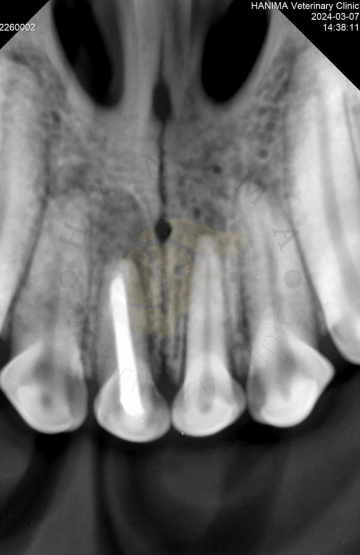

Léčba kořenových kanálků (endodoncie) je léčba, která zahrnuje odstranění infikované dřeně z kořenového kanálku zubu, sterilizaci (dezinfekci) kanálku a nahrazení odstraněné tkáně zubním materiálem. Kořenový kanálek je přístupný přes korunku zubu. Jakmile je kořenový kanálek naplněn zubním materiálem, přístup přes korunku je vyplněn (obnoven), aby se zabránilo dalšímu přístupu bakterií do kořenového kanálku. Konečným cílem je zabránit bakteriím v pronikání do zubu. Standartní terapie kořenových kanálků umožňuje domácímu mazlíčkovi zachovat si zub (ačkoli již nežije) a zachovat jeho funkci, protože strukturální integrita zubu byla zachována.

Když si pes zlomí zub a obnaží dřeň, bakterie a zbytky z úst proniknou do středu zubu. V důsledku toho se rozvine bolestivý zánět dřeně (pulpitida), který nakonec způsobí odumírání nervů a krevních cév (nekróza dřeně). Bakterie pronikají ven z kořenového hrotu (špička kořene obklopená kostí) a infikují kost kolem kořene (apikální parodontitida). Pulpitida i apikální parodontitida jsou velmi bolestivé. Vzhledem k tomu, že infekce zubu a následně také infekce kosti kolem kořene je vysoce pravděpodobná, zlomené zuby s obnažením dřeně by měly být co nejdříve ošetřeny buď standardní terapií kořenových kanálků tj. endodonticky, nebo extrakcí.